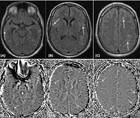

CADASIL Misdiagnosed as Multiple Sclerosis

Anthony Wong, BS; Jacquelyn Johnson, MS, CGCAnthony Wong, BS; Jacquelyn Johnson, MS, CGC